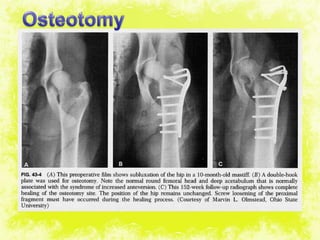

Osteotomy

Acetabular cartilage

viable

not viable

THRHemireplacement arthroplasty

Bipolar arthroplasty

Radiography

Bonescan

•Symptomatic treatement: bed rest, NSAIDS.

•Displacement or Angulation Osteotomy in early

stages.

•Hemireplacement arthroplasty

•THR.